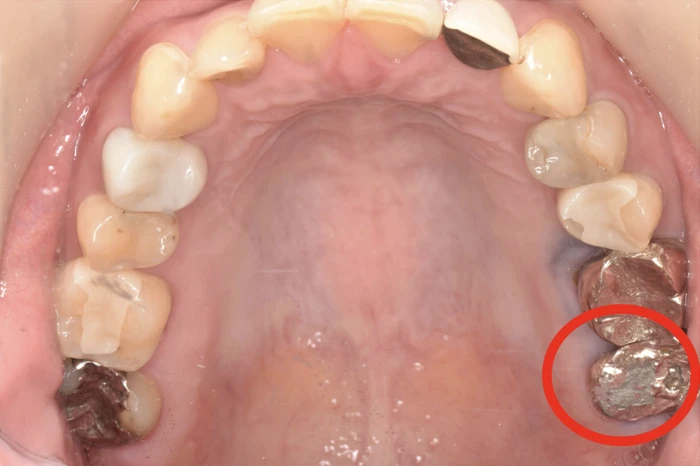

銀歯が削れる?

「銀歯って金属なのに削れるの?」そう疑問に思う方は多いと思います。

結論から言うと、銀歯は削れます。

なぜ金属が削れるのか?

歯ぎしり・食いしばりの力は非常に強く、自分の体重以上の力がかかることもあります。

この強い力が毎晩のように繰り返されることで、金属であっても徐々に削れていきます。

実は「歯の方が硬い」

ここが重要なポイントです。天然の歯(エナメル質)は非常に硬い組織です。

一般的な歯科用金属と比較すると、エナメル質の方が硬い場合もあります。

そのため、以下のような現象が起こります。

- 天然歯 vs 銀歯=銀歯が削れる

削れると何が起こるのか?

銀歯が削れることで、以下のような悪循環が生まれます。

- 噛み合わせが変わる

- 特定の歯に負担が集中する

- さらに歯ぎしりが悪化する